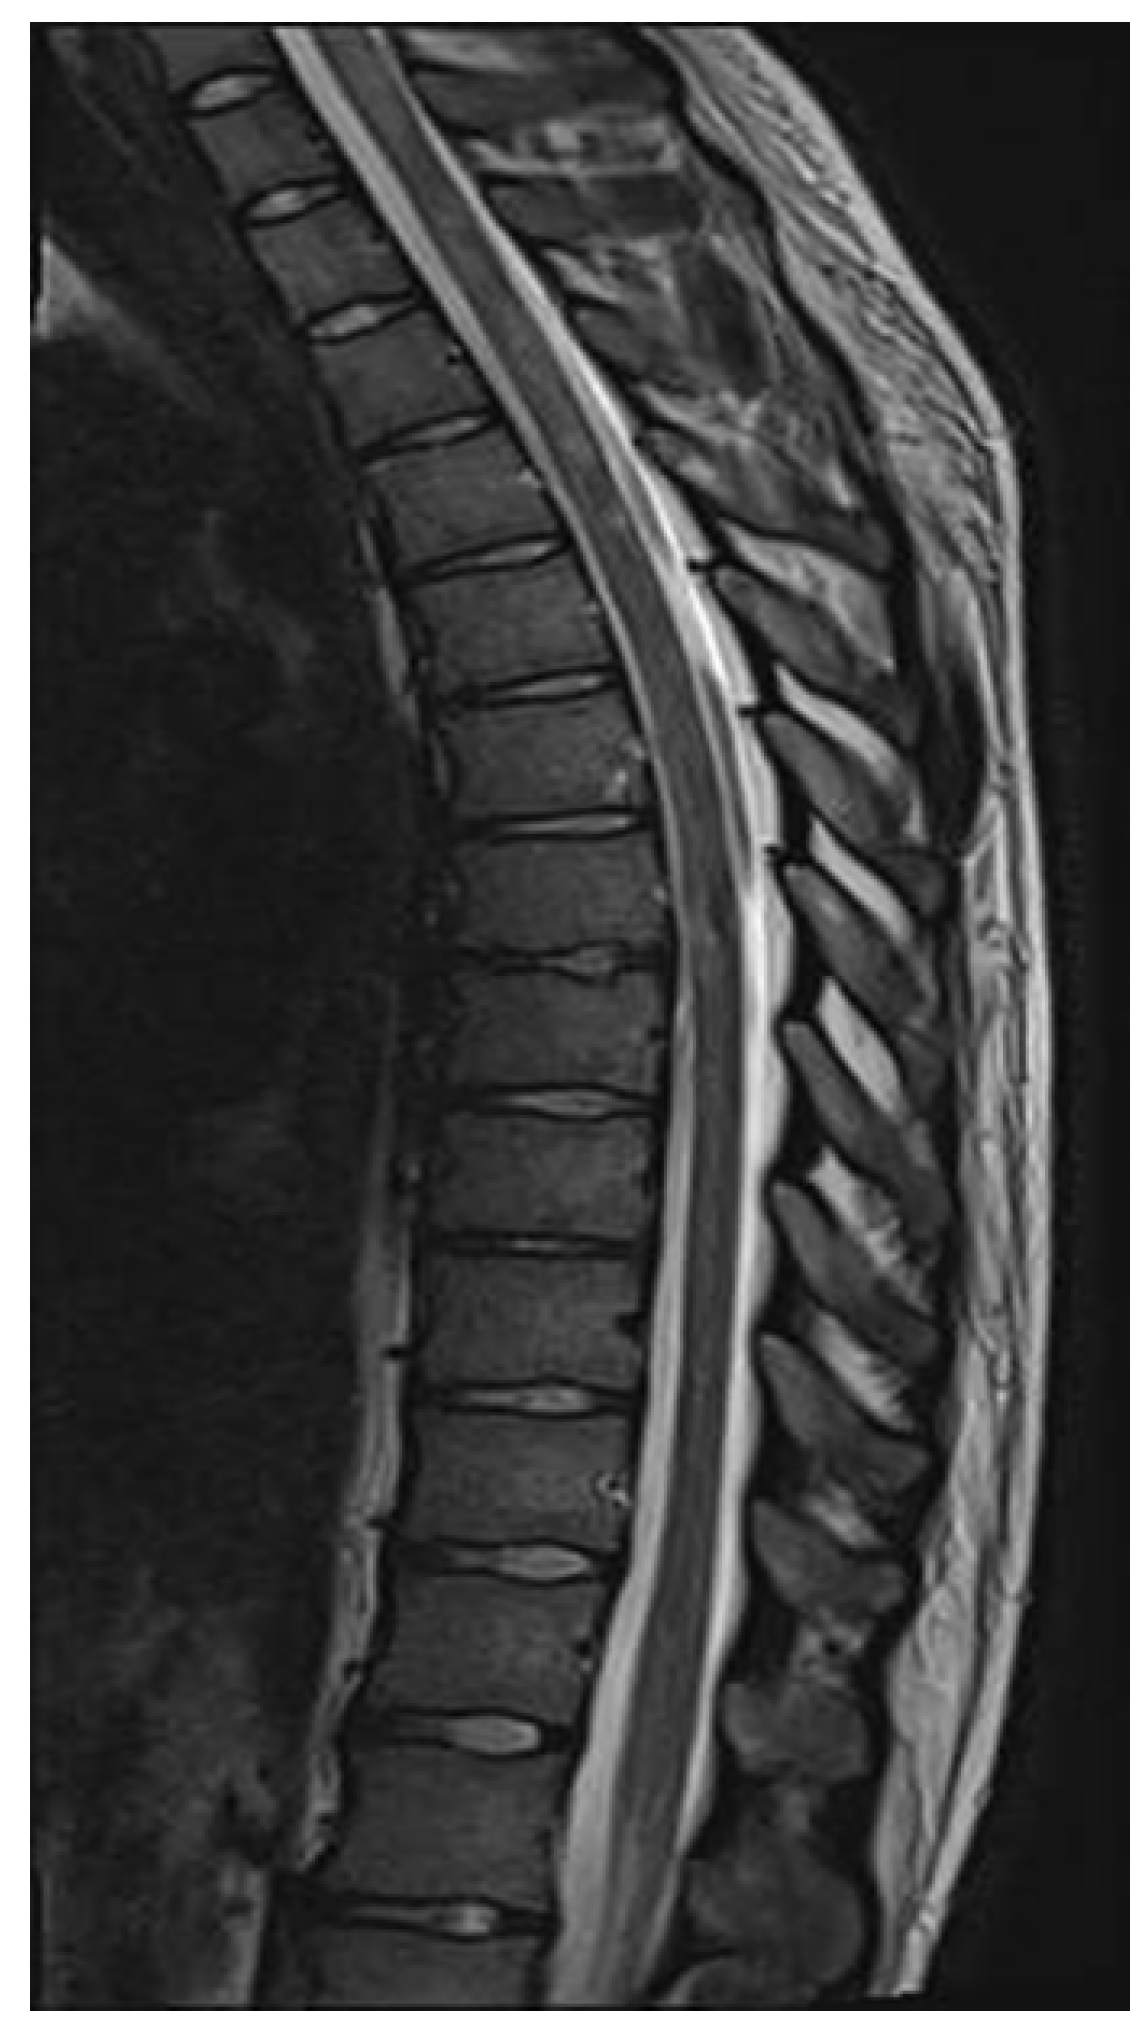

2. Case Report

| Myelitis | longitudinally extensive enhancement, central cord lesion, or H-sign, conus lesion |